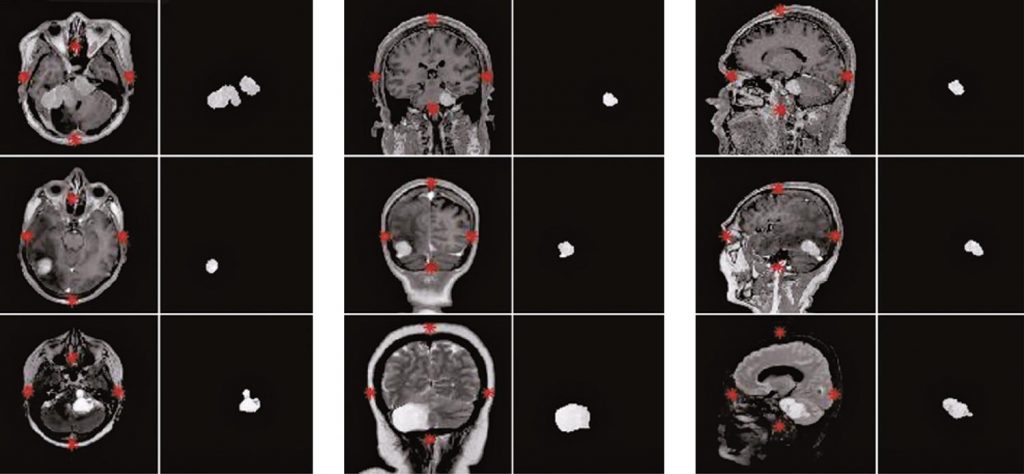

Foram utilizadas 130 imagens de ressonância magnética nas sequências T1c, T2 e FSPRG T1c e nos planos axial, sagital e coronal de pacientes acometidos com câncer cerebral. Os algoritmos empregaram técnicas de correção de contraste, normalização de histograma e binarização, para desconectar estruturas adjacentes do cérebro e realçar a região de interesse. A segmentação automática foi realizada por meio da detecção por coordenadas e por média aritmética da área. Operadores morfológicos foram utilizados para eliminar elementos indesejáveis e reconstruir a forma e a textura do tumor. Os resultados foram comparados com as segmentações manuais de dois médicos radiologistas, para determinar a eficácia dos algoritmos implementados.

Os acertos foram de 89,23% na correspondência entre a segmentação obtida e o padrão-ouro.

É possível localizar e delimitar a região tumoral de forma automática, sem necessidade de interação com o usuário baseado em dois métodos inovadores de detecção dos extremos do cérebro e de exclusão dos tecidos não tumorais em imagens de ressonância magnética.